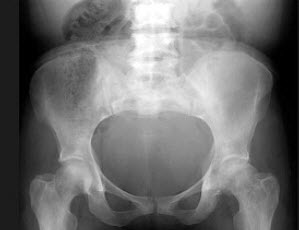

224、单项选择题

女,38岁,慢性疾病史,结合图像,最可能的诊断是()

A.Legg-Perthes病

B.骨梅毒

C.关节结核

D.镰状细胞贫血

E.强直性脊柱炎